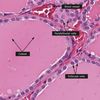

27

What is N?

Lateral ventricle

28

What is A?